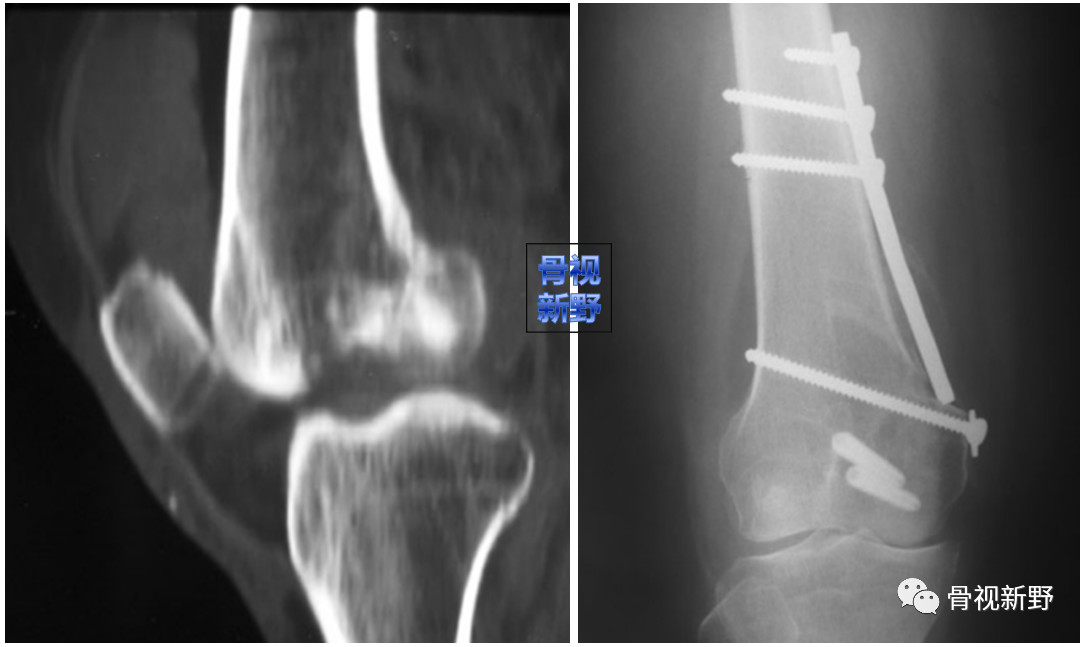

影像诊断:部分Hoffa骨折X线片不能提供明确的诊断,漏诊率较高。需要CT或MRI检查,并根据患者的病史、查体及影像学检查予以确诊。

部分Hoffa骨折普通X光片易漏诊

CT扫描在矢状位、轴位容易发现骨折及骨折线的走形方向